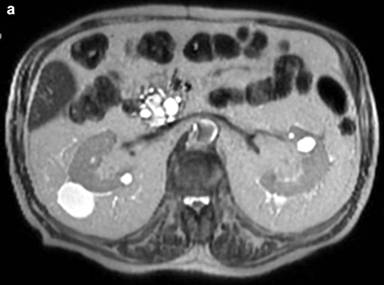

The medical history of the patient began when he was 60-year-old. Following the diagnosis of diabetes mellitus, an abdominal ultrasound (US), showed the incidental finding of a cystic lesion, 30 mm in diameter, located in the pancreatic head. Magnetic resonance imaging (MRI) and cholangiopancreatography showed a cystic lesion, 30 mm in diameter, without mural nodules and communicating with a non-dilated main pancreatic duct. Ultrasound-guided fine needle aspiration (FNA) of the cystic fluid showed high levels of CEA (104 ng/mL; normal value <5) and amylase (1230 U/L; normal value <70). Taking into account the age of the patient (having a long life-expectancy), the cystic size (30 mm) and the diagnosis of a branch-duct IPMN, the patient underwent surgery. At laparotomy, neither careful palpation of the gland or intra-operative ultrasound showed the cystic lesion. Thus, the surgery consisted of an exploratory laparotomy (April, 1999). The patient was enrolled in a surveillance program with yearly abdominal US scans. Five years after surgery, US showed a cystic lesion (diameter 17 mm) of the pancreatic head without mural nodules and Wirsung dilatation. Subsequent evaluations of the cystic lesion with US scans showed stable disease until April 2013, that is 14 years after the diagnosis and the exploratory laparotomy. At this time, the cystic lesion showed an increase in size (from 17 mm in diameter to 29 mm x 32 mm). Magnetic resonance imaging plus cholangio-pancreatography showed additional cystic enlargement (60 mm x 26 mm) and diffuse Wirsung duct dilatation (8 mm) (Figures 1 and 2). Finally, endoscopic ultrasound (EUS) confirmed a cystic lesion 3 cm in diameter communicating with a diffusely dilated main duct (maximum diameter 15 mm), revealing the presence of the “fish-eye” sign and several contrast-enhancing mural nodules inside the cyst. Endoscopic ultrasound FNA did not show malignant cells. Taking into consideration the presence of these “high-risk-stigmata” according to the Fukuoka guidelines [3], the patient underwent surgery; a total pancreatectomy was performed due to the involvement of the entire pancreatic gland. Pathological examination revealed a mixed-IPMN diffused throughout the entire pancreas with high grade dysplasia, and a micro-invasive carcinoma (<1 mm) of the pancreatic head. The postoperative course was uneventful and the patient was discharged on postoperative day 12. At six months from surgery, the patient is alive and well, without recurrences.

Figure 2. Fourteen years after diagnosis, axial MR images showed the cystic lesion of the pancreatic head and its communication (white arrow) (a) with a diffusely dilated main pancreatic duct (b). |